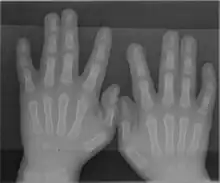

Syndactyly is a condition wherein two or more digits are fused together. It occurs normally in some mammals,[1] but is an unusual condition in humans. The term is from Ancient Greek σύν (syn) 'together' and δάκτυλος (daktulos) 'finger'.

Syndactyly can be simple or complex.[2]

- In simple syndactyly, adjacent fingers or toes are joined by soft tissue.

- In complex syndactyly, the bones of adjacent digits are fused. The kangaroo exhibits complex syndactyly.

Syndactyly can be complete or incomplete.

- In complete syndactyly, the skin is joined all the way to the tip of the involved digits.

- In incomplete syndactyly, the skin is only joined part of the distance to the tip of the involved digits.